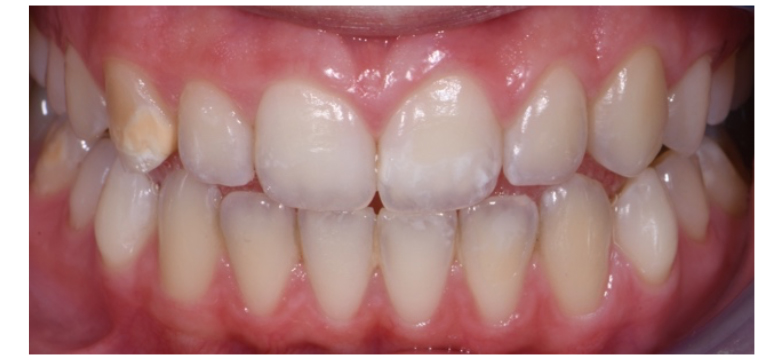

La paziente ha continuato a ripete controlli mensili, igiene orale professionale a cadenza semestrale e mostra tutta la sua soddisfazione nei risultati ottenuti (Fig. 4).

A distanza di 5 mesi ripetiamo una seduta di igiene orale professionale e mediante un’indagine fotografica valutiamo lo stato di salute dello smalto che risulta stabile (Fig. 5).